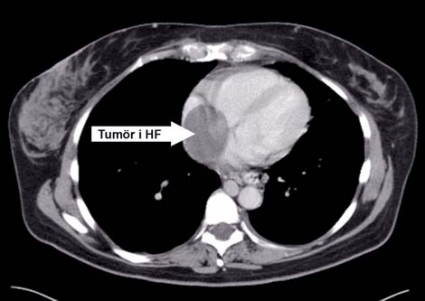

Patienten försämrades dock med tilltagande kraftig leversvikt; ny datortomografi verifierade leverstas och ascites. Det som tidigare uppfattats som en vena cava-trombos bedömdes nu som en heterogen tumörmassa (Figur 1), vilken också omfattade uterusområdet. Den tumörsuspekta tromben fyllde ut hela vena cava inferior och sträckte sig in i höger förmak (Figur 2).